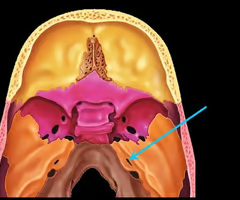

Pterygoid processes of sphenoid bone (trough - shaped anchor for chewing muscles)

Palatine process of maxilla (helps form hard palate with palatine bones)

Palatine bones

Vomer

Vomer